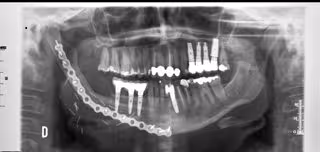

Las reconstrucciones mandibulares realizadas a través de tecnologías en 3D son "mucho más" precisas y sencillas, el tiempo quirúrgico se reduce en varias horas y el resultado es una mandíbula con oclusión dental conservada y contornos mandibulares simétricos y naturales, lo que supone "una revolución" en la vida de los pacientes, según el doctor de la Unidad de Cirugía Oral y Maxilofacial & Odontología & Periodoncia Hospitalaria del complejo hospitalario Ruber Juan Bravo, Javier Arias Gallo.

Ahora las técnicas de imagen médica en tres dimensiones dan una imagen "muy precisa" de la forma de los tejidos en los que se trabaja, pues mediante el uso del ordenador para la simulación tridimensional de la mandíbula y el peroné, se pueden diseñar con "gran precisión" la posición, angulación y colocación de cada uno de los segmentos óseos, y diseñar previamente a la intervención una placa de osteosíntesis que se adapte exactamente a los contornos óseos, ha destacado el doctor Arias.